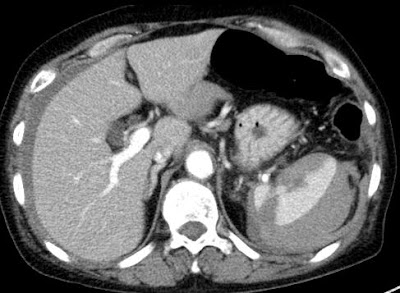

Right adrenal haemorrhage following blunt abdominal trauma. Rare finding (R > L). Hyperdense lesion without enhancement (no prior unenhanced scan in this case).